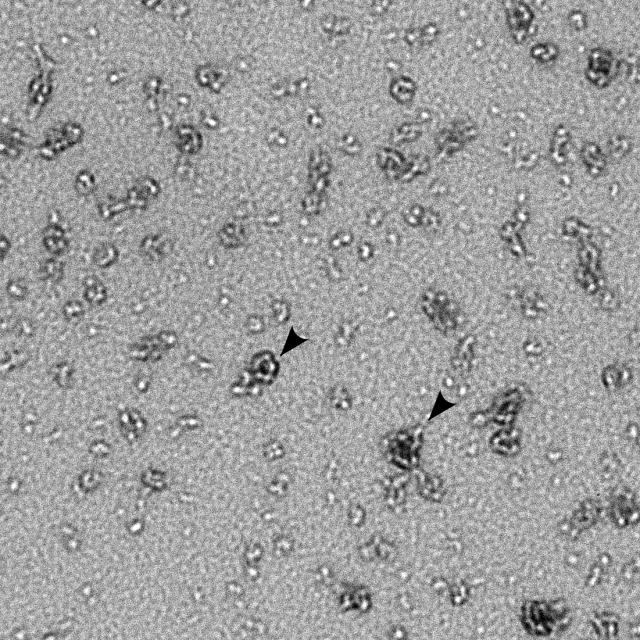

سببها بكتيريا (خلايا حية صغيرة) تسمى الكلاميديا تراخوماتيس.